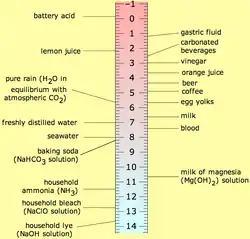

The most common cause of erosion is by acidic foods and drinks. In general, foods and drinks with a pH below 5.0–5.7 have been known to trigger dental erosion effects.[6] Numerous clinical and laboratory reports link erosion to excessive consumption of such drinks. Those thought to pose a risk are soft drinks, some alcohol and fruit drinks, fruit juices such as orange juice (which contain citric acid) and carbonated drinks such as colas (in which the carbonic acid is not the cause of erosion, but citric and phosphoric acid).[7] Additionally, wine has been shown to erode teeth, with the pH of wine as low as 3.0–3.8.[6] Other possible sources of erosive acids are from exposure to poorly regulated chlorinated swimming pool water,[8] and regurgitation of gastric acids.[9] In children with chronic diseases, the use of medicines with acid components is a risk factor too.[10] Dental erosion has also been recorded in the fossil record and was likely caused by the consumption of acidic fruits or plants.[1]

Extrinsic acid erosion is when the source of acid originates from outside of the body.[11] Acidic food and drink lowers the pH level of the mouth resulting in demineralisation of the teeth. A variety of drinks contribute to dental erosion due to their low pH level. Examples include fruit juices, such as apple and orange juices, sports drinks, wine and beer. Carbonated drinks, such as colas and lemonades, are also very acidic and hence have significant erosive potential. Foods such as fresh fruits, ketchup and pickled food in vinegar have been implicated in causing acid erosion.[12] Frequency rather than total intake of acidic juices is seen as the greater factor in dental erosion; infants using feeding bottles containing fruit juices (especially when used as a comforter) are therefore at greater risk of acid erosion.[12]